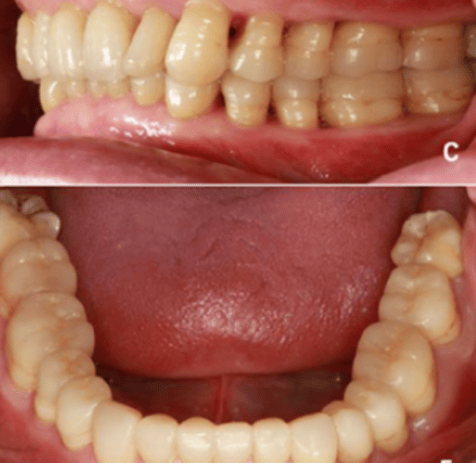

颌重建:适用于重度磨损而引起食物嵌塞的患者。用该方法恢复正常的咬合垂直距离、颌面形态与牙齿外形后,食物嵌塞会随之消失。